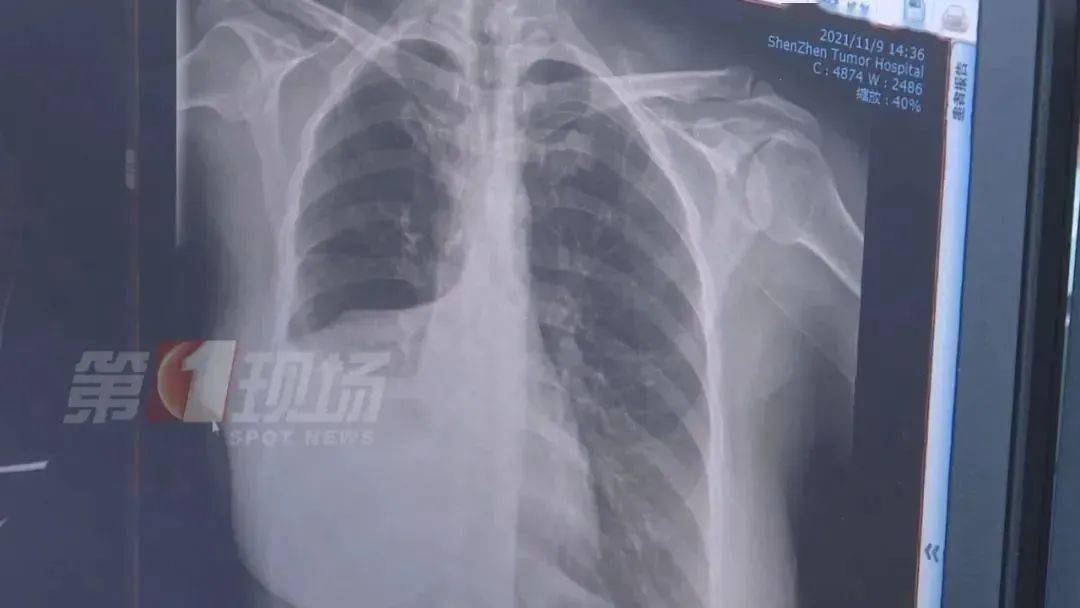

女士做了增强CT后 , 确实发现肺部有一个五公分左右的肿瘤 ,医生诊断为肺癌 , 目前为中期偏早 , 建议她进行切除手术 。